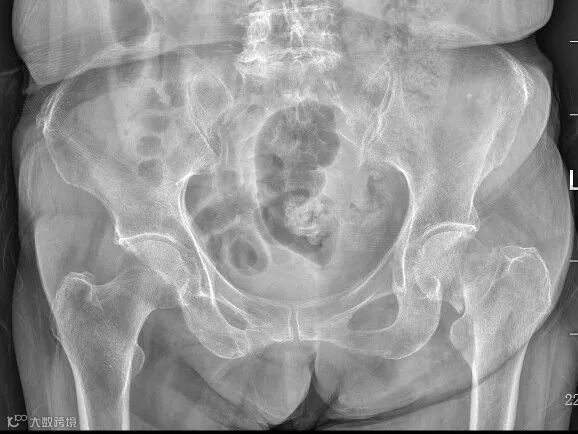

第一次术前影像资料